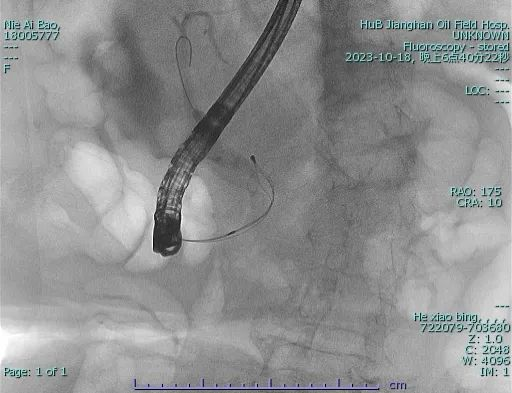

我院介入放射科于2021年5月成立,于2022年3月24日实施第1例ERCP手术,至今已实施40余例ERCP手术,为多位胆总管结石及梗阻性黄疸患者解除病痛,得到了患者的大量好评。ERCP手术具有手术时间短、恢复快、并发症少、住院时间短的优点。只要患者有需求,且患者的身体条件许可,我院医生都愿意为患者实施手术为患者解除疾苦。10月18日,我院介入放射科和手术麻醉科协作,在省人民医院邓涛教授指导下连续完成三台ERCP手术,成功为患者解除胆总管结石痛苦。术后患者均恢复良好,目前3名患者均已康复出院。

ERCP全称经内镜逆行胰胆管造影,是指将十二指肠镜插至十二指肠降部,找到十二指肠乳头,由活检管道内插入造影导管至乳头开口部,注入造影剂后x线摄片,以显示胰胆管的技术。